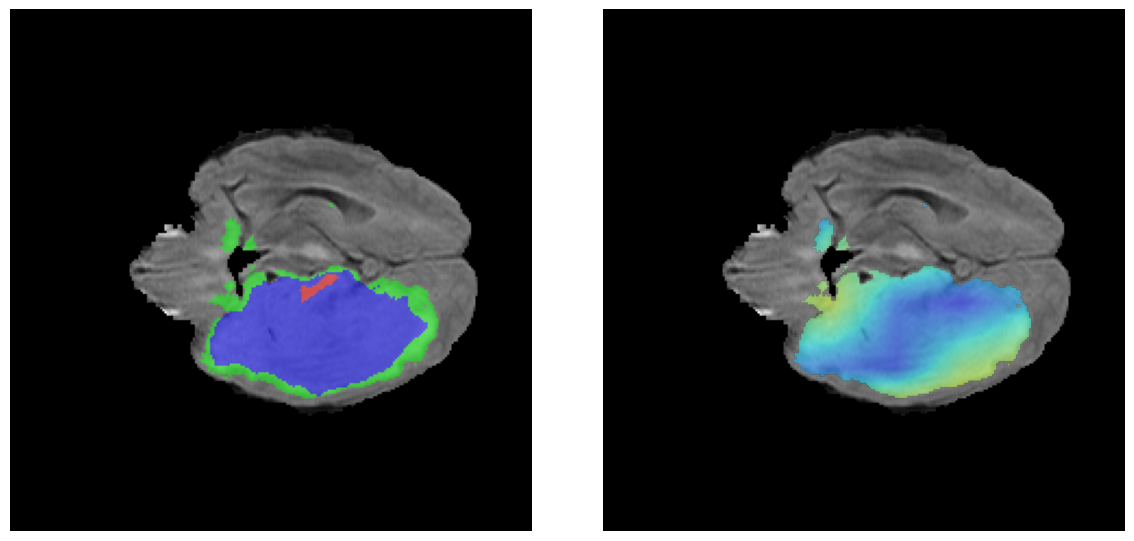

Mapas de Explicabilidad (Grad-CAM++)

Visualización de las regiones de atención del modelo que validan su razonamiento clínicamente relevante

Ejemplos LGG - Atención Difusa en Edema Peritumoral

LGG Grad-CAM++ 1 LGG Grad-CAM++ 2 LGG Grad-CAM++ 3 LGG Grad-CAM++ 4 LGG Grad-CAM++ 5 LGG Grad-CAM++ 6

Para casos LGG, la atención del modelo es más difusa y se concentra principalmente en la región de Edema Peritumoral (verde), consistente con la naturaleza más infiltrativa y menos agresiva de estos tumores.